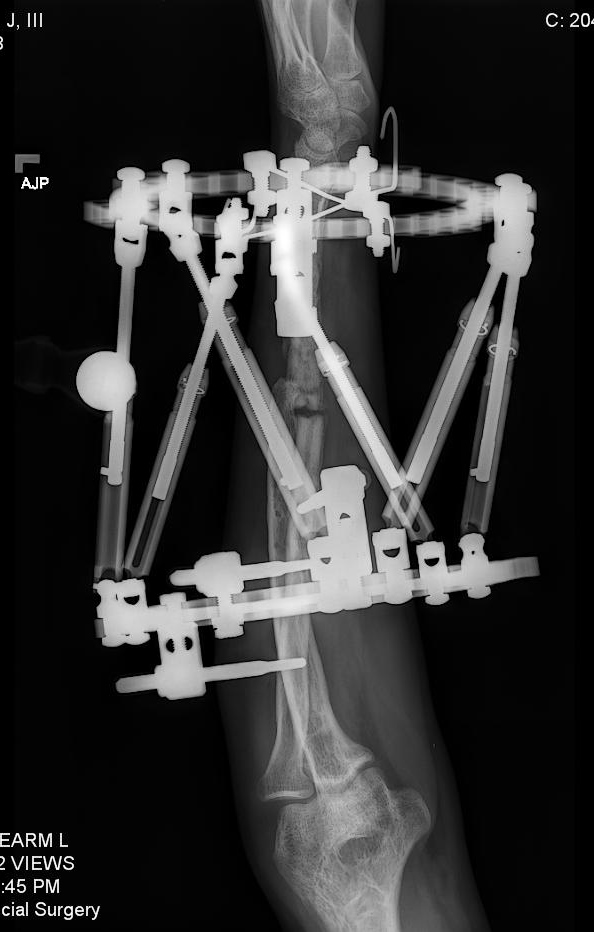

I was in a serious car accident in 2010 and broke both arms, both legs, pelvis, vertebrae and ribs. I was flown to a trauma 2 center in NJ. After being put back together from the initial accident, I healed for 3 months until I searched out Dr. Rozbruch at HSS. My right leg was short and angled due to the trauma. My left arm was a non-union and deformed. Sitting with Dr. Rozbruch for the first visit was amazing. He was confident in time that all of my issues could be repaired. It took multiple surgeries but a couple years later and he was right, HSS and Dr. Rozbruch fixed every single issue. I went from being told I may never walk again at the original hospital to now back to surfing, water skiing and playing basketball. Never in a million years did I think I would have such an incredible outcome. To add to the already stellar Dr. Rob Rozbruch and HSS, I became friends with Dr. Rob Rozbruch and together we created a new product and company over the past 5 years to aid patients in their healing. It is a device that aids patients in healing from lower limb injuries.